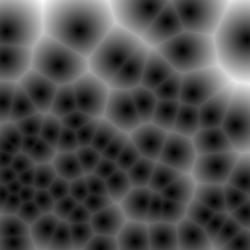

4.1.1 Voronoi labels

A Voronoi diagram is a partitioning of a plane into convex polygons (Voronoi cells) according to the distance to a set of points in the plane. There is exactly one point (seed point) in each cell and all points in a cell are closer to its seed point than other seed points. In our task, the detected points in an image can be treated as seed points to calculate the Voronoi diagram as shown in Fig. 1(b). For each Voronoi cell, assuming that the corresponding nucleus is located within the cell, then the Voronoi edges separate all nuclei well and the edge pixels belong to the background. This assumption holds for most of the nuclei because the detected points are around the centers and nuclear shapes are nearly convex (Fig. 3(b)).

Assigning the Voronoi edges as background pixels and the detected points (dilated with a disk kernel of radius 2) as nuclei pixels, we obtain the Voronoi point-edge label (Fig. 3). All other pixels are ignored during training. Note that although the pixels on the Voronoi edge between two touching nuclei may not necessarily be background, the edges are still helpful in guiding the network to separate the nuclei. The Voronoi labels aim to segment the central parts of nuclei and are not able to extract the full masks, because they lack the information of nuclear boundaries and shapes. To overcome this weakness, we generate another kind of labels that contain this complementary information.